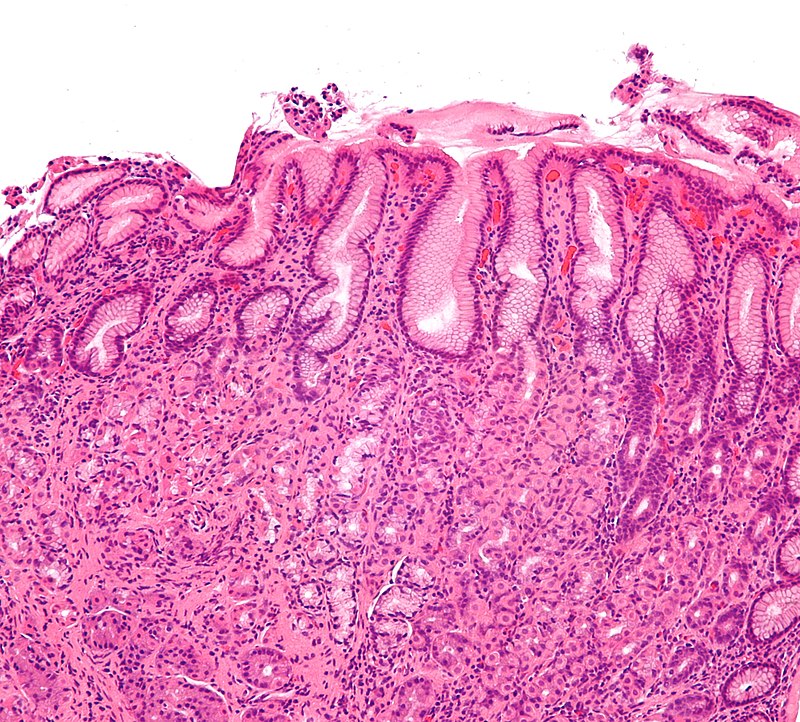

Chronic Gastritis

Chronic gastritis is due to inflammation of stomach mucosa.

Chronic Autoimmune Gastritis

Chronic autoimmune gastritis is the autoimmune destruction of gastric parietal cells, which are found in the stomach body and fundus.

Chronic autoimmune gastritis is linked to parietal cell and/or intrinsic factor antibodies.

Clinical features of chronic autoimmune gastritis include:

- Atrophy of mucosa with intestinal metaplasia

- Achlorhydria with antral G-cell hyperplasia and elevated gastrin levels

- Megaloblastic (pernicious) anemia because of lack of intrinsic factor

Patients with chronic autoimmune gastritis have increased risk for gastric adenocarcinoma (intestinal type).